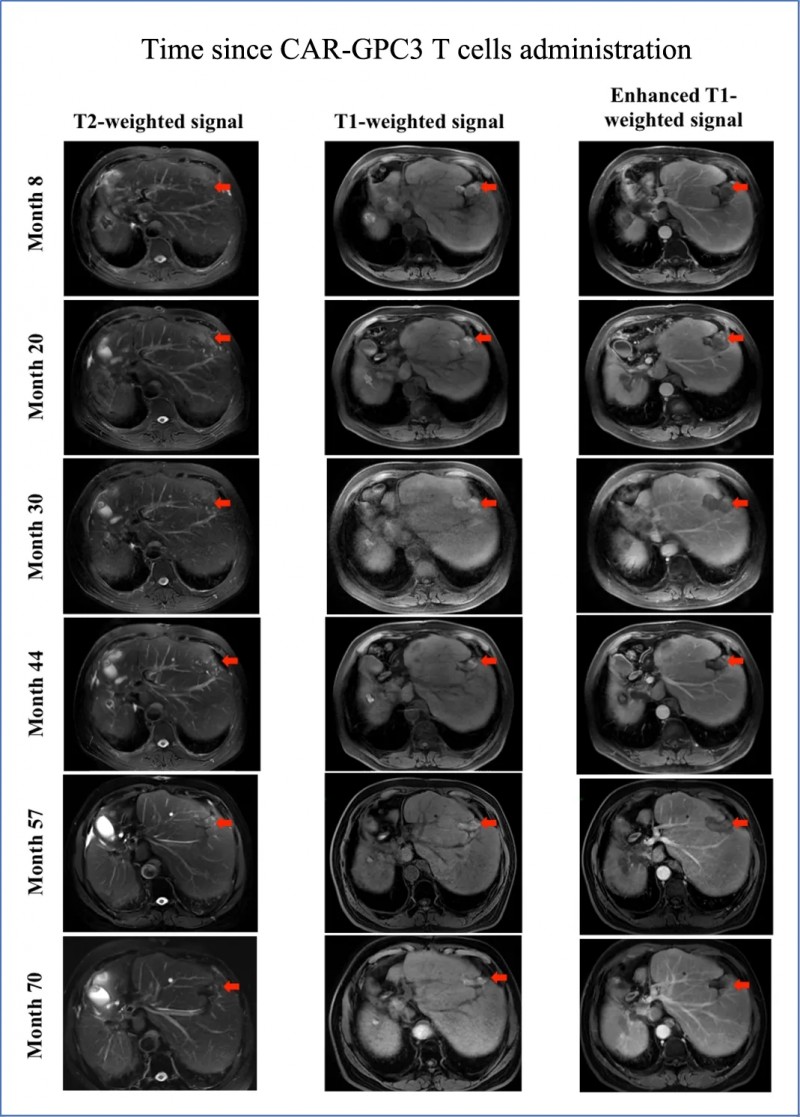

KT032是全球首创的国研新型靶向间皮素(MSLN)的CAR-T细胞疗法,属于多链DAP-CAR-T技术路线。在体外细胞杀伤试验与异种移植模型中,该疗法(尤其由自然杀伤细胞免疫球蛋白样受体截短体与DAP12结合形成的多链DAP-CAR-T),相比其他由DAP12、DAP10或CD3ζ相关自然杀伤细胞激活受体介导的CAR-T,展现出更优的细胞毒性与肿瘤杀伤能力。近期,KT032公布首次人体临床试验的振奋数据——在卵巢癌与间皮瘤患者中,疾病控制率(DCR)达100%。

该研究共纳入8例晚期难治性患者(7例卵巢癌、1例间皮瘤),所有患者均至少接受过2种标准治疗(如化疗、靶向药)后复发或进展,且经病理确认肿瘤细胞MSLN表达≥15%(MSLN为KT032的精准靶点)。

结果显示:8例患者疾病控制率达100%,无1例出现快速进展,意味着CAR-T细胞成功抑制肿瘤进展;其中2例实现“部分缓解”(肿瘤缩小≥30%),部分缓解率33.3%;4例达到“疾病稳定”(肿瘤未增大或略有缩小),6例肿瘤得到有效压制。生存数据同样亮眼,患者中位无进展生存期(PFS)达5.5个月,中位总生存期(OS)达10.5个月,远超同类患者预期生存时间。此外,部分患者治疗后癌抗原125(CA125)水平显著下降,整体治疗有效率远超传统方案。

值得关注的是,两位患者的疗效尤为突出:患者1肝转移灶缩小31%,且腹腔积液完全消失;患者2可测量病灶总最大直径缩小42%(详见下图)。

▲图源“BMC”,版权归原作者所有,如无意中侵犯了知识产权,请联系我们删除